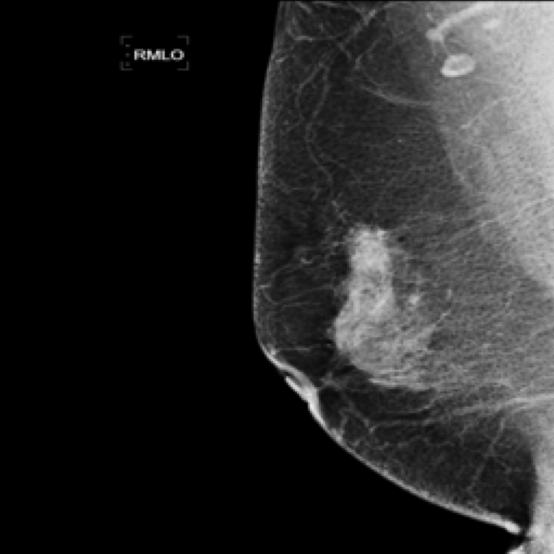

Mammography Imaging. In radiological examinations, multiple views are captured to thoroughly represent lesions. For mammography, these typically include four views: left mediolateral oblique (LMLO), left craniocaudal (LCC), right mediolateral oblique (RMLO), and right craniocaudal (RCC). To ensure dataset completeness and versatility for various tasks, we retained all views in their original form, irrespective of the presence breast lumps. However, views without breast lumps are not involved in this study.

5.9 ViKL Provides Evidence for Clinical Decision

In our earlier sections, we discussed how ViKL enhances the image branch’s capability for detailed feature extraction by using text and manifestations that describe localized lumps. To directly observe this enhanced feature extraction ability, we utilize the class activation map (CAM) [62], a common tool for visualizing neural network activations. Specifically, we employ Grad-CAM [63] to generate activation maps from the third layer of the ResNet50 model, which has been fine-tuned using ViKL on the MKVL dataset. Additionally, for accurate visualization and comparison, we include markings of lumps as annotated by professional radiologists. The results of this visualization are showcased in Fig. 6. These visualizations demonstrate ViKL’s effective localization of small lesions, highlighting its refined ability to capture minute features in medical imaging.